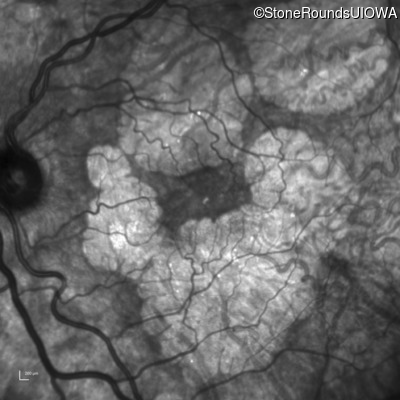

Infrared Fundus Photograph - Right - 20/40 -2

Exemplar